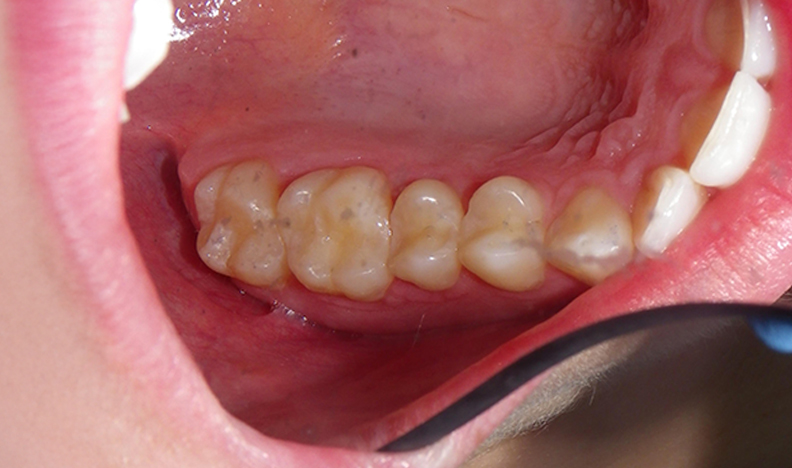

After educating the patient on the decay risks of this behaviour, oral hygiene instruction and a recommendation for a daily fluoride rinse, she can now take action to prevent any new cavities from developing for the rest of her life. There were many areas of decay between other teeth that we elected not to fill due to their small size, and hopefully they remain arrested / remineralized! (Aluminum oxide Air abrasion via PrepStart, 32% Phosphoric acid etch with Benzalkonium Chloride and AllBond Universal adhesive from Curion, Esthet-X Flowable A2 liner from Dentsply, Simplishade Medium resin core from Kerr).